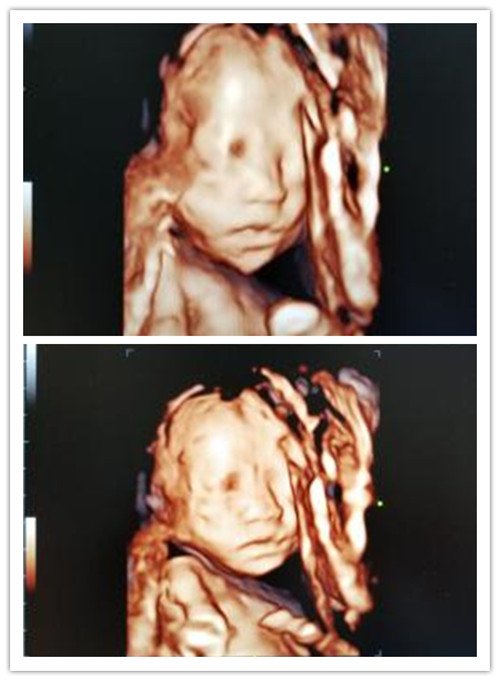

2、妊娠子宫的诊断、胎儿系统筛查及胎儿四维成像。早、中、晚期正常妊娠中胎儿生长、发育情况及其羊水、脐带、胎盘的监测。异常的妊娠有流产、异位妊娠(宫外孕)、胎儿生长发育迟缓、胎儿畸形(无脑畸形、脑积水、脊椎裂、消化道或泌尿系畸形等)、前置胎盘、胎盘出血、羊水量异常、脐带绕颈、滋养叶疾病(葡萄胎、恶性葡萄胎、绒毛膜癌等)。

高端四维彩超机GE-炫光E8